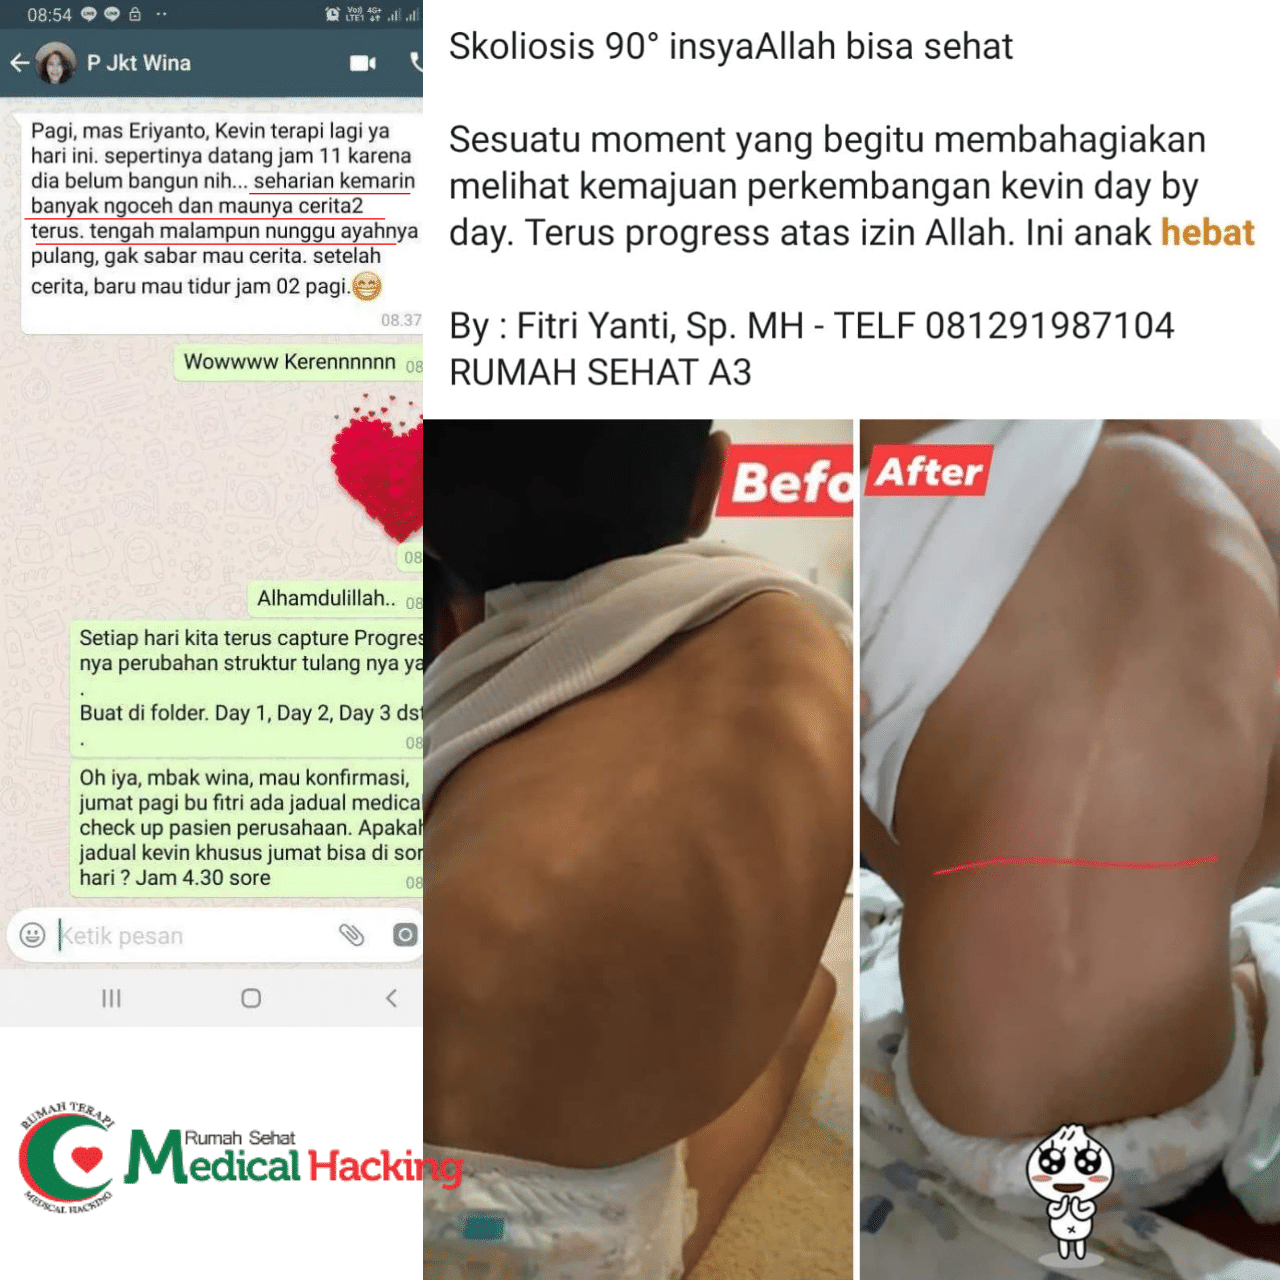

Kalau kamu pengen cara yang lebih efektif, kamu bisa cari terapi khusus yang dirancang buat ngurangin nyeri Radang Persendian secara alami. Banyak tempat terapi sekarang yang punya pendekatan modern tanpa obat kimia berat. Salah satunya adalah medicalhacking yang fokus banget bantu banyak orang ngurangin nyeri dan pulih lebih cepat lewat teknik terapi yang udah disesuaikan dengan kondisi setiap orang.

Medicalhacking juga melayani terapi stroke jakarta dengan pendekatan yang lembut tapi hasilnya nyata banget. Mereka ga cuma fokus ke satu bagian tubuh, tapi bener-bener ngeliat keseluruhan kondisi kamu biar hasil terapinya maksimal. Banyak pasien yang ngerasain tubuhnya lebih ringan, nyeri berkurang, dan gerakan jadi lebih bebas setelah dapet terapi yang konsisten.